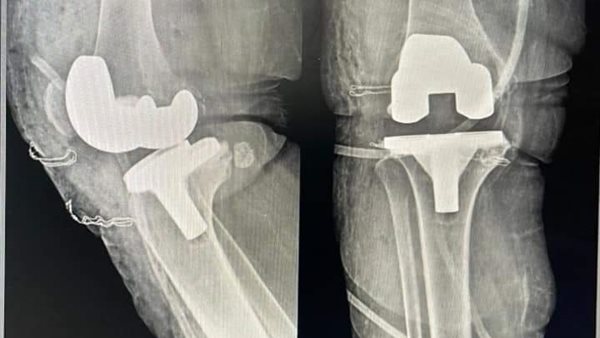

نجح أطباء مستشفى الزرقا المركزي بمحافظة دمياط بقيادة الدكتور عمرو شاهين، مدير المستشفي، من إجراء عملية تركيب مفصل صناعي لمريض بالمستشفي لأول مرة وذلك في ضوء توجيهات الدكتور السيد عبد الجواد، مدير مديرية الشئون الصحية والسكان بمحافظة دمياط، وبتضافر الجهود المبذولة من الدكتورة دعاء المحلاوي، مسؤول قوائم الإنتظار بمديرية الشئون الصحية والسكان بمحافظة دمياط.

وقال الدكتور عمرو شاهين، مدير مستشفي الزرقا المركزي بمحافظة دمياط، أن العملية الجراحية جاءت بمشاركة الفريق الطبي بقسم جراحات العظام والتخدير بالمستشفى لتركيب المفصل للمريض بعد أن كان يعاني من خشونة متقدمة في الركبة أدت إلى تشوه، لافتًا إلي أنه تم خروج المريض من المستشفى وهو بحالة صحية جيدة وقادر على الحركة.